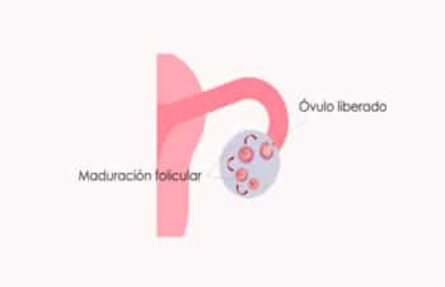

¿Cómo saber cuándo estás ovulando? Señales de ovulación

¿Qué es la anovulación y cómo afecta a la fertilidad?